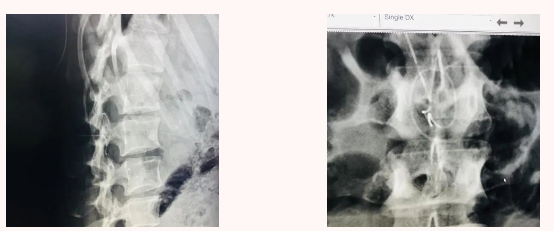

2、在上级医师的指导下重新摆体位在C臂机辅助下尝试拔管,未能拔出,C臂机摄片可见导管折弯,请麻醉科、影像科、骨科、外科、妇产科、医务科等相关科室会诊。

图3 正、侧位DR摄片